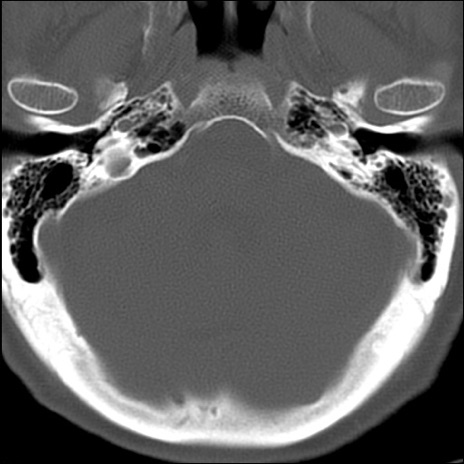

症例48 頚椎CT(横断像)

頚椎CT